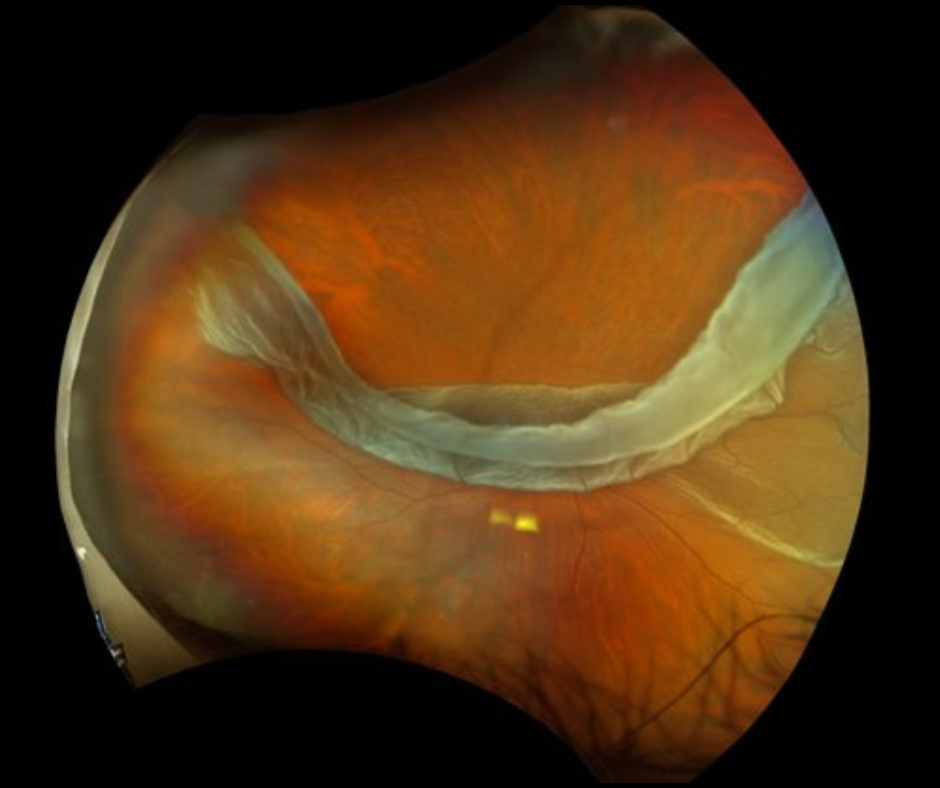

- ROP is a retinopathy eye disease that can affect premature infants born weighing less than 1250 grams or before 31 weeks of gestation. Abnormal blood vessel growth can cause bleeding and scarring in the eye, and in the most severe cases, lead to retinal detachments with potentially permanent vision loss.

- ROP is an eye disease that arises as a result of incomplete development of the retina (the light-sensing tissue that lines the inside of the back of the eye). Babies who are born before 32 weeks of gestation (I.e., 2 or more months premature) or with a birth weight less than 3 pounds are most at risk. Incomplete retinal development may lead to the growth of abnormal blood vessels, which in turn can bleed or scar. If not diagnosed and appropriately treated, ROP can lead to permanent vision loss or blindness due to retinal detachment. Between 500 and 1000 infants go blind from ROP in the United States each year. The rates of vision loss are higher in poorer countries.

In experienced hands, the chance of blindness from ROP is exceedingly low. The conventional treatment is laser surgery to the retina, to induce regression of abnormal blood vessels. In some cases, injections of special medication (so-called anti-VEGF medication) into the eye are used for the same purpose. The choice and timing of these treatments are determined by the severity of the ROP and the overall health of the infant. In severe cases, more advanced retinal surgery may be required to repair retinal detachment.